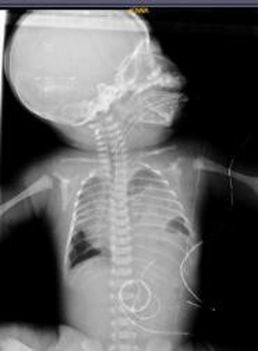

After the surgical procedure, an adequate clinical evolution was observed, where he received high-frequency ventilation support for 3 days, and then non-invasive ventilation for 1 day. Control chest X-ray showed correction of the defect and an improvement in left lung expansion. (Figure 4). He remained in the unit for 28 days, where he received comprehensive management and was discharged medically, oxygen-dependent by nasal cannula at low flows.

Figure 4 Postoperative Chest X-ray

Correction of left diaphragmatic defect.

Source: Hospital de Especialidades de las Fuerzas Armadas N°11